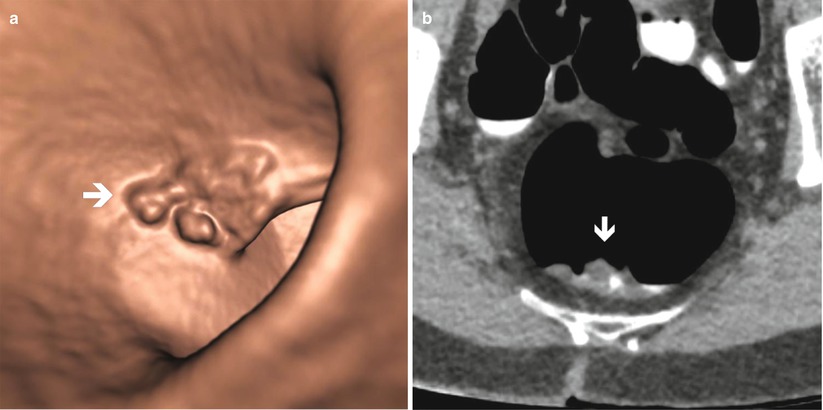

Benign Diseases Of The Colon And Rectum Incl Ct Colonography

Ct Colonographic Images Show A Large Proved Polyp That Simulates